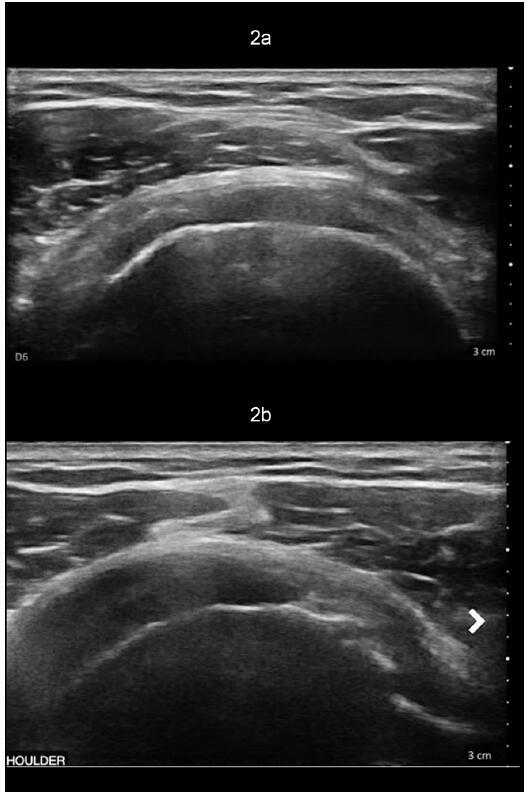

肩关节粘连性囊炎(AC)是一种常见的疾病,通常以临床病程延长和患者发病率高为特征,导致较高的社会经济负担。尽管有许多研究评估了各种治疗方式,但优化的治疗算法仍然难以捉摸。类似地,肩关节骨性关节炎(OA)表现出类似的临床和甚至更高的社会经济影响。诊断成像和短期疼痛管理方法的进步尚未产生有效的长期疾病改善疗法。随着肩关节骨性关节炎患者平均年龄的下降,人们对旨在减轻症状、提高生活质量和可能推迟侵入性手术干预的再生治疗越来越感兴趣。本文概述了AC和盂肱骨关节炎(GHOA)的病理生理学,并附有回顾性试点案例研究,证明了一种称为RELIEF®治疗的新型骨科方法的有效性。这种创新的方法产生了有希望的短期结果,包括治疗后6个月时多平面肩关节活动度(ROM)和功能评分的显著改善。RELIEF®治疗包括诊断性动态超声,以识别筋膜中的瘢痕或异常,并结合使用冷冻保存的微细化人羊膜悬浮液异体移植物(hAMA)和Isolyte晶体IV液的水解剖技术。在超声直接引导下,使用局麻药(2%利多卡因加肾上腺素1:20万)进行多次注射,目的是溶解纤维化瘢痕组织并将同种异体移植物输送到患处。治疗前和治疗后ROM评估由有执照的物理治疗师使用角度计进行。测量分别在基线(治疗前)和治疗后2周、2个月、4个月和6个月进行。此外,记录美国肩肘外科医生(American Shoulder and肘部外科医生)评分和视觉模拟量表(visual analogue scale, VAS)疼痛评分。随后在第二次RELIEF®治疗后4个月进行肩部MRI(无造影剂),以评估任何放射学上的显著变化,并将这些发现与患者报告的症状和整体功能状态的变化联系起来。

Adhesive capsulitis (AC) of the shoulder is a prevalent condition often characterized by a prolonged clinical course and significant patient morbidity, leading to a high socioeconomic burden. Despite numerous studies evaluating various treatment modalities, an optimized treatment algorithm remains elusive. Similarly, osteoarthritis (OA) of the shoulder presents a comparable clinical and an even higher socioeconomic impact. Advances in diagnostic imaging and short-term pain management options have not yielded effective long-term disease-modifying therapies. With the decreasing average age of patients suffering from glenohumeral OA, there is a growing interest in regenerative treatments aimed at alleviating symptoms, enhancing quality of life, and potentially postponing invasive surgical interventions. This paper provides an overview of the pathophysiology of both AC and glenohumeral osteoarthritis (GHOA), accompanied by a retrospective pilot case study demonstrating the efficacy of a novel orthobiologic approach known as the RELIEF® treatment. This innovative approach yielded promising short-term outcomes, including significantly improved multi-planar shoulder range of motion (ROM) and functional scores at six months post-treatment. The RELIEF® treatment involves diagnostic dynamic ultrasound to identify scarring or abnormalities in the fascia together with a hydrodissection technique using a combination of cryopreserved micronized human amniotic membrane suspension allograft (hAMA) and Isolyte crystalloid IV fluid. Under direct ultrasound guidance, local anesthetic (2% lidocaine with epinephrine 1:200,000) is utilized to perform multiple injections aimed at lysing fibrotic scar tissue and delivering the allograft to affected areas. Pre- and post-treatment assessments of ROM were conducted by a licensed physical therapist utilizing a goniometer. Measurements were taken at baseline (before treatment) and subsequently at two weeks, two months, four months, and six months post-treatment. Additionally, American Shoulder and Elbow Surgeons (ASES) scores and visual analog scale (VAS) pain ratings were recorded. An MRI of the shoulder (without contrast) was subsequently performed 4 months following the second RELIEF® treatment to evaluate for any radiographically significant changes and to correlate these findings with change in patient-reported symptoms and overall functional status.